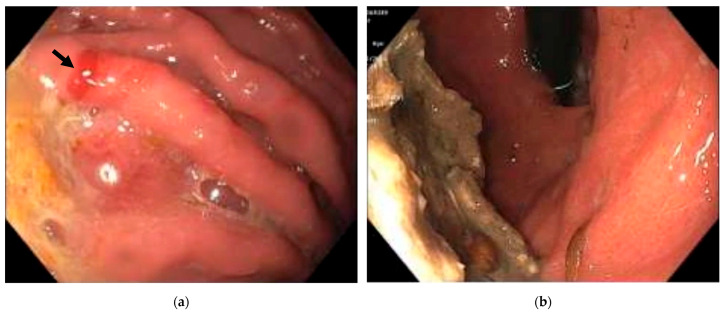

Background and Clinical Significance: Sarcina ventriculi is a rare Gram-positive coccus that thrives in acidic environments such as the human stomach. It has been increasingly identified in individuals with delayed gastric emptying and has been reported in association with various gastric disorders. However, its exact pathogenic role is not fully understood and remains controversial. Case Presentation: We present two cases of patients, one with a small bowel obstruction and the other with epigastric pain, both diagnosed with Sarcina ventriculi infection by histological examination of gastric biopsies. The patients were managed with a combination of antibiotics and a proton pump inhibitor, resulting in symptom resolution and clearance of Sarcina ventriculi upon follow-up examinations. Conclusions: This report explores the pathogenicity of Sarcina ventriculi by documenting its presence in symptomatic patients without other identifiable pathogens and demonstrating complete symptom resolution following targeted therapy. These findings raise the possibility of Sarcina ventriculi's pathogenic potential under specific clinical conditions, suggesting it may act as more than a benign colonizer.